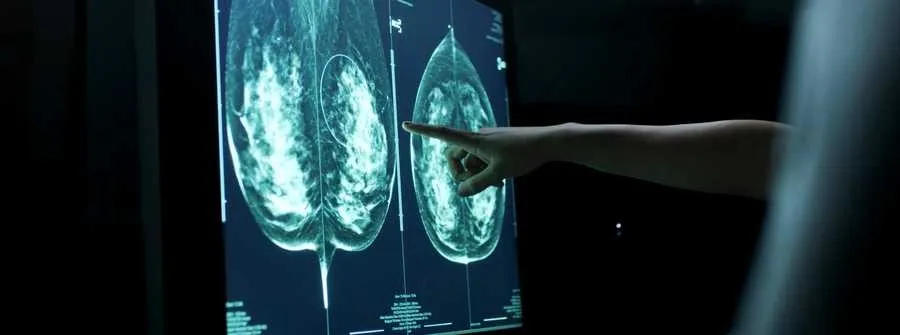

Ал скрининг — ауруды ерте кезеңінде анықтау үшін денсаулығына шағымы жоқ адамдардың медициналық тексерілуі. Оның чекаптан айырмашылығы — белгілі бір жас тобына кіретін адамдар, тіркелген емханасындағы медбикенің шақыруымен тексеруден өтеді. Мысалы, жатыр мойны обыры ауруына скрининг 30-70 жас аралығындағы әйелдер арасында 4 жылда 1 рет өткізіледі.

Ұлттық ғылыми онкологиялық орталықтың меңгерушiсi Индира Құсайынованың сөзінше, елімізде қатерлі ісікпен ауыратын және ауруын асқындырып келетін пациенттердің саны артпаса, кемімей тұр. Кейбір пациенттер III немесе IV сатысында ғана медициналық көмекке жүгініп жатады.

“Бұл – қазіргі онкологиялық қызметтің өзекті проблемаларының бірі. Сондықтан да профилактикалық тексерулер мен дәрігерге уақытында қаралу – онкологиямен күрестегі ең маңызды қадам,”— дейді ол.